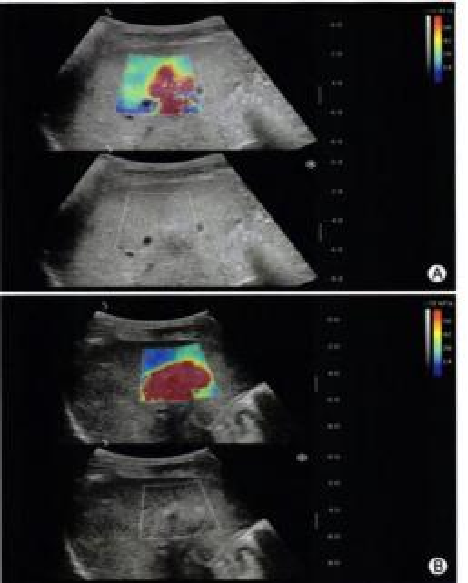

平面波超微细血流显像

能够提供更多真实的组织细小及末梢血管的血流信息,直观的观察组织内部的血管架构及血流形态的情况,提供临床更多有价值的诊断信息。

临床应用:

肿瘤鉴别诊断(肝脏、肾脏、甲状腺、乳腺、 涎腺等)

淋巴结评价(炎症、肿瘤)

肌骨系统临床诊断和疗效监测(关节、滑膜、韧带、肌肉炎症、 损伤等)

斑块内新生血管评估

超声介入术前进针方案提供血流参考信息

超声介入术后疗效评估